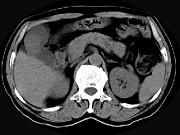

问题 男,45岁,右季肋区疼痛,Murphy征阳性,B超提示胆囊息肉,CT所见如图,最可能的诊断是()

选项 A.胆囊息肉 B.胆囊癌 C.慢性胆囊炎 D.胆囊转移癌 E.胆囊腺肌增生症

答案 B